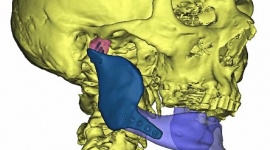

Chirurdzy z Kliniki Chirurgii Szczękowo-Twarzowej i Plastycznej Uniwersyteckiego Szpitala Klinicznego w Białymstoku dokonali rekonstrukcji kości żuchwy przy użyciu tytanowego implantu, który powstał indywidualnie na potrzeby danego pacjenta w drukarce 3D.

Chirurdzy z Kliniki Chirurgii Szczękowo-Twarzowej i Plastycznej Uniwersyteckiego Szpitala Klinicznego w Białymstoku dokonali rekonstrukcji kości żuchwy przy użyciu tytanowego implantu, który powstał indywidualnie na potrzeby danego pacjenta w drukarce 3D. Jest to pierwszy w Polsce implant wykonany tą technologią. Stworzyła go białostocka spółka ChM.

Indywidualny wszczep został zastosowany u 78 letniego pacjenta, któremu z powodu choroby nowotworowej usunięto znaczną część żuchwy. Bezpośrednio po zabiegu kikuty żuchwy unieruchomiono tytanową płytą rekonstrukcyjną. Płyta utrzymywała prawidłową pozycję kikutów żuchwy jednak nie odtwarzała ubytku kostnego i defektu twarzy.

Jak podkreśla kierownik Kliniki, prof. Stanisława Zyta Grabowska, standardowym postępowaniem w takim przypadku jest jednoczasowe odtworzenie ubytku kostnego wolnym własnym przeszczepem kości (np. kości strzałkowej) na zespoleniach mikrochirurgicznych. U danego pacjenta zastosowanie takiego rozwiązania było niemożliwe z uwagi na poważne obciążenia ogólnoustrojowe. Po pewnym czasie użytkowania, tytanowa płyta pękła.

Wtedy pojawił się pomysł zastosowania innowacyjnego rozwiązania, polegającego na stworzeniu implantu indywidualnego dla tego chorego w technologii druku 3D.

Implant powstał na podstawie obrazu z tomografii komputerowej, na bazie którego po odpowiednim przetworzeniu, specjaliści z ChM stworzyli jego projekt. Na tej podstawie w drukarce 3D „wydrukowano” implant ze stopu tytanu będący idealnym odwzorowaniem brakującego fragmentu kości.

Prace nad implantem trwały blisko dwa tygodnie. Zarówno pacjent jak i lekarze, są zadowoleni z końcowego wyniku leczenia. Mężczyźnie przywrócono rozwarcie szczęk i niemal całkowicie estetyczny wygląd twarzy.

Specjaliści przyznają, że w przyszłości widzą możliwość zastosowania tej innowacyjnej metody u innych pacjentów (onkologicznych i urazowych). Przede wszystkim u takich, u których przeprowadzenie rekonstrukcji kości według obowiązujących standardów nie może być brana pod uwagę ze względu na poważne przeciwwskazania miejscowe lub ogólne.